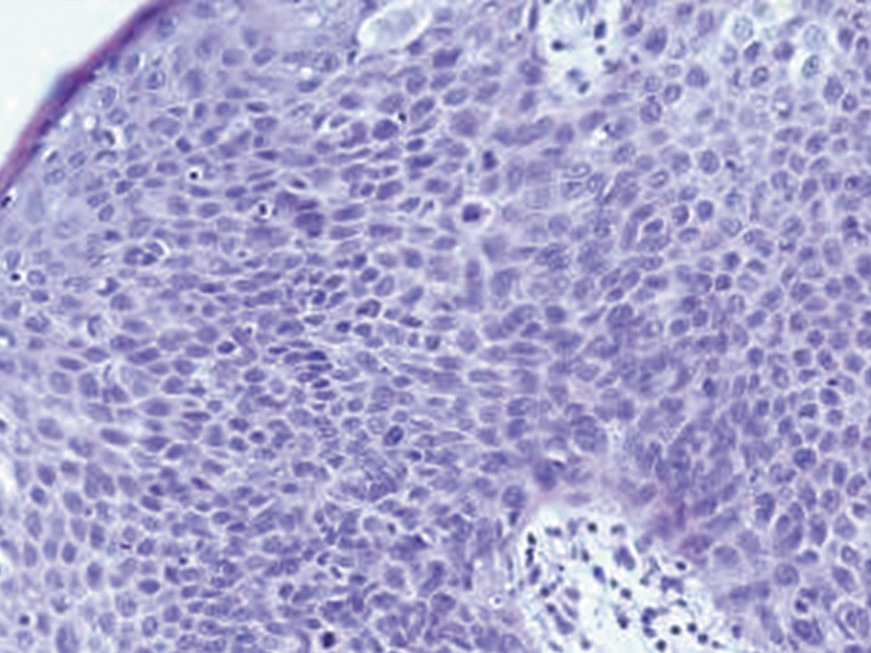

In Group B patients, the hyperplastic epithelium demonstrated focal proliferation of epithelial cells with hyperchromatic polymorphic nuclei against a background of acanthotic, papillomatous, and dystrophic features. These changes included loss of polarity, partial disruption of epithelial stratification starting from the basal layer and extending to upper layers, involving areas of varying size and epithelial thickness. Low-grade dysplasia was diagnosed in 6 patients, high-grade dysplasia in 16 patients, among which 5 cases (31.3%) showed combined foci of low- and high-grade dysplasia, and 6 cases (37.5%) revealed areas of covering epithelium ulceration with marked reactive inflammation in the subepithelial stroma manifested by diffuse infiltration of segmented leukocytes, lymphocytes, and histiocytes along with occasional eosinophilic granulocytes and macrophages. In specimens with intact epithelial lining, mixed inflammatory cell infiltration of the lamina propria was also observed, varying in intensity and cellular composition. The epithelial changes characteristic of Group B patients are illustrated in Figures 2 and 3.

Figure 3. Changes in the submucosa in the lesions of the lip in patients of Group B. There is a high degree of dysplasia in the stratified squamous epithelium. In the proper plate of the mucosa, capillaries of various sizes with ectatized free lumens, pronounced diffuse lymphoplasmocytic infiltration. Staining with hematoxylin and eosin. ×100.

Рисунок 3. Изменения подслизистой основы в очагах повреждения губы у пациентов группы Б. В многослойном плоском эпителии дисплазия высокой степени. В собственной пластинке слизистой разнокалиберные капилляры с эктазированными свободными просветами, выраженная диффузная лимфоплазмоцитарная инфильтрация. Окраска гематоксилином и эозином. ×100.

In ulcerated areas of stratified squamous epithelium within pathological foci, the subepithelial stroma exhibited ectatic congested capillaries and polymorphous inflammatory infiltration of varying intensity. In regions of lip vermilion border mucosa with epithelial dysplastic changes, vascular distribution demonstrated marked variability, alternating between hypovascularized zones of the lamina propria and angiomatosis fields characterized by clusters of tightly packed small capillaries surrounded by pericytes and fibroblast-like cells.